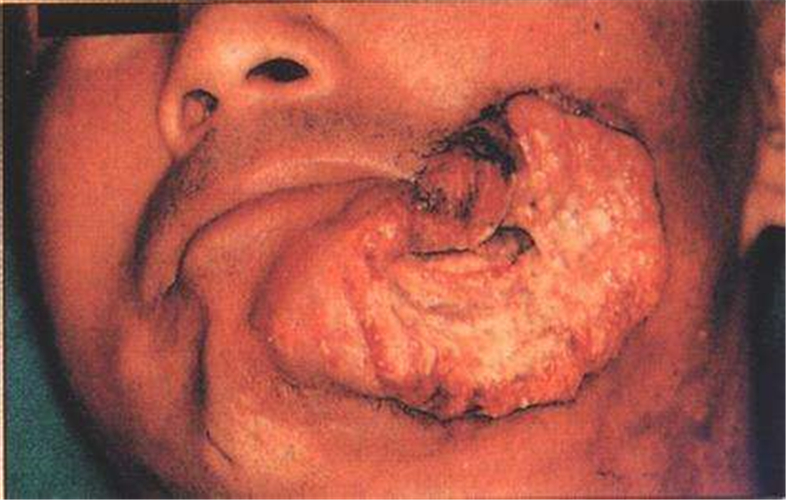

頰癌圖片

男子頰癌術前

男子頰癌口腔

男性頰癌什麼樣

男性頰癌